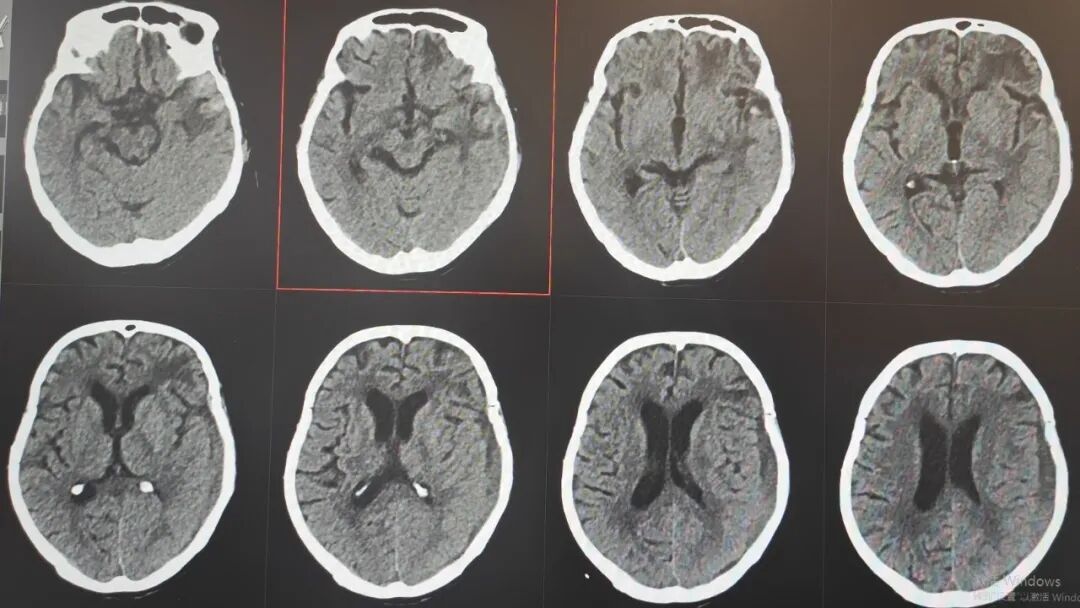

89岁的吴阿婆(化名)突发意外,被发现时已意识不清、陷入昏迷。家人发现后,紧急将其送往漳州第三医院,检查结果令人揪心:重型颅脑损伤、脑内大面积出血,加之O型Rh(D)阴性熊猫血、严重贫血……多重致命高危因素叠加,病情十分危重。

如此复杂凶险的状况,在常人看来几乎已是绝境!但漳州第三医院神经外科团队没有放弃,考虑到阿婆身体条件极差、血型特殊、手术风险难以预估,最终摒弃常规开颅方案,为她量身制定了个体化精准保守治疗方案,在绝境中为生命守住一线希望。

那段日子,病情几度反复、险象环生,医护人员寸步不离守在床前,24小时紧盯生命体征,精细调整每一步治疗方案,昼夜不敢有丝毫松懈。在一次次与死神的拉锯中,他们凭着耐心与坚守,终于等来了转机:阿婆从深度昏迷慢慢睁开双眼,从卧床不起到能在搀扶下缓缓起身,每一个微小的进步,都藏着无数个日夜的坚守与温暖,让绝境之中绽放出生命的微光。